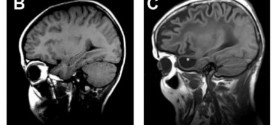

LEUCODISTROFIA

La leucodistrofia. Las leucodistrofias destruyen el sistema nervioso central (cerebro y médula espinal) en niños y adultos. Afecta a la mielina, la sustancia blanca que rodea los nervios como una funda aislante. Las leucodistrofias son enfermedades raras que afectan las células del cerebro. Específicamente, las enfermedades afectan la vaina de mielina, el material que rodea y protege las células nerviosas. …